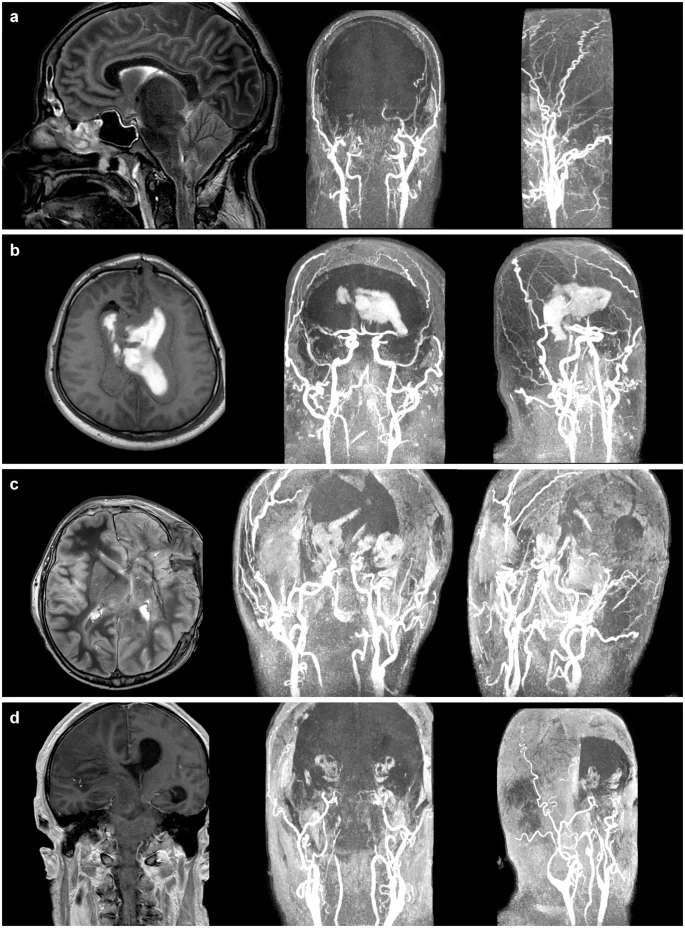

그림 5. 조영제를 이용한 뇌 혈관조영술. 뇌사한 환자들에게는 뇌 혈관에서의 혈액 흐름이 관찰되지 않는다. 이들을 사망으로 보아야 하나? 장기기증에 있어 이는 중요하다.*

* M. Pan, Nat. Comm, 2021.